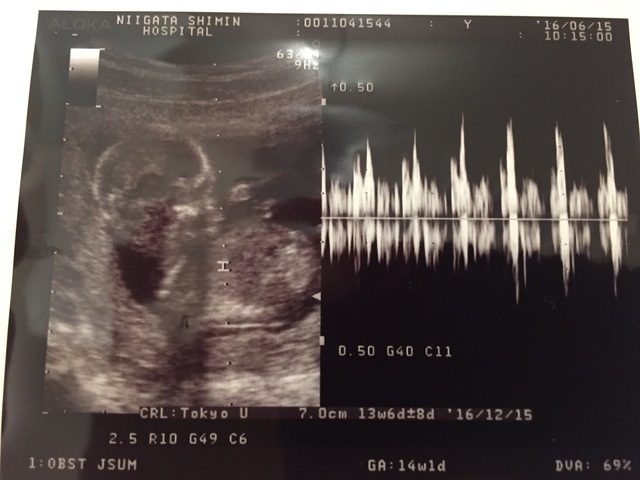

14週1日(14w1d・男の子)|kmom さん(18歳)

エコー写真撮影時のエピソード:

ずっと男の子の気がしていて結構早くから男の子のシンボルが見えて愛おしかった。毎回検診が楽しみでよく動く子でしゃっくりも良くする子でした!

体重が増えすぎて何回か注意されたこともありましたがなんとか産むまでには10kg以内でおさめれました(笑)